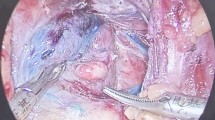

In the experimental group, nano-carbon suspension (Canaline, Chongqing Laimei Pharmaceutical Co., Ltd., H20041829, 1 mL: 50 mg) was injected into each thyroid lobe at two points (approximately 0.1 mL per point), ensuring to avoid intravascular administration. After 3–5 minutes, the thyroid and surrounding lymph nodes were black-stained (Fig. 3).

Intraoperative contrast enhancement with nano-carbon suspension in thyroid surgery. This image shows the application of nano-carbon suspension during total thyroidectomy and cervical lymph node dissection for papillary thyroid carcinoma. Injecting nano-carbon into the thyroid gland and surrounding tissues enhances visual contrast, distinctly delineating the parathyroid glands from adjacent structures. The black staining facilitates the precise identification and preservation of the parathyroid glands, reducing the risk of inadvertent injury during surgery.